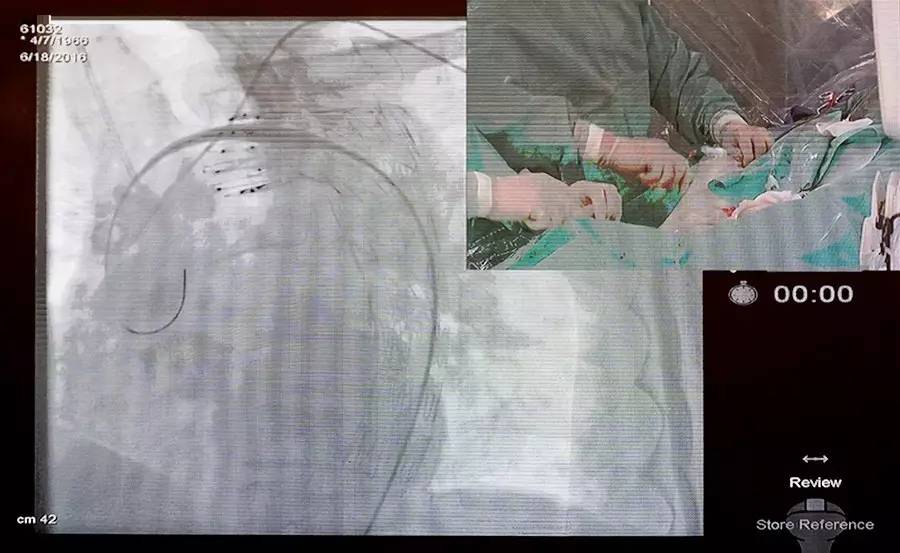

今天下午,在CCCP&NCF 2016的冠心病介入论坛中,进行了精彩的主动脉夹层及CTO手术直播。

在第一场的主动脉夹层手术直播中,沈阳军区总医院王效增教授担任主要术者,陶杰、李智医生担任助手。患者为50岁男性,突发左侧胸痛2天;胸痛向后背部及腹部脐水平放散,程度剧烈,伴大汗;既往糖尿病病史6年,高血压病史2年;入院查体:T 37℃,HR 80次/分,BP 183/119 mmHg;化验检查:血肌酐 104.40 umol/L,D-二聚体 3.4 mg/L;心脏超声:主动脉硬化改变,EF 0.65;诊断:Standford B型降主动脉夹层。

术后造影